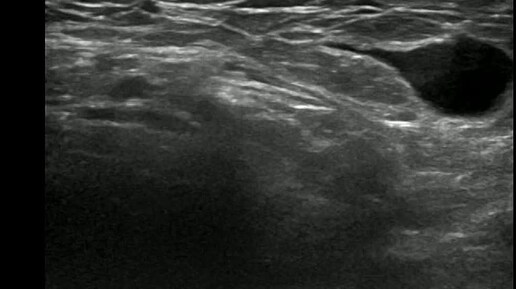

Видео к статье: Гидроцеле канала Нукка. https://dzen.ru/a/aDAxMOvxqQcgJkGG

Ультразвуковые находки от врача УЗД Зорина Я.П.